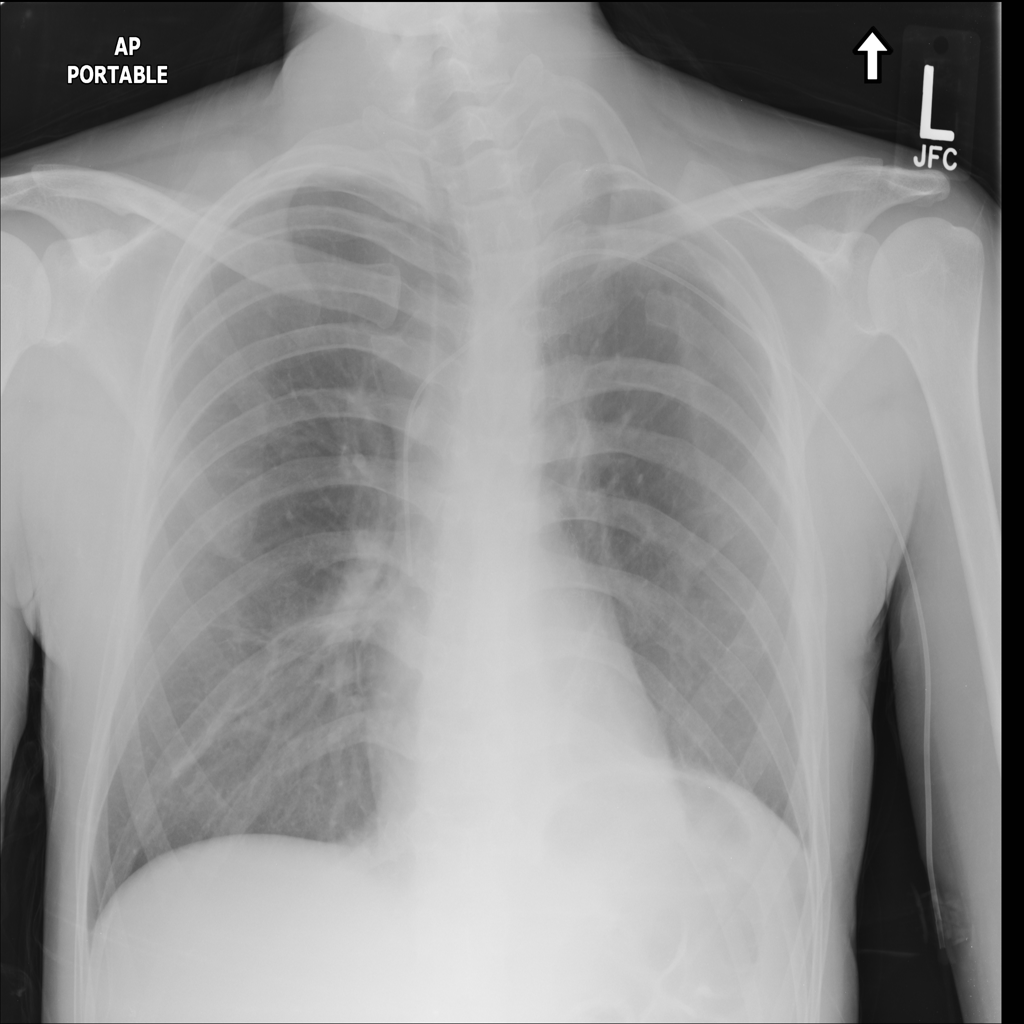

Consolidation

Consolidation refers to air-space filling that makes part of the lung appear denser on imaging.

Showing up to 90 reference images for Consolidation.

PAT-531A · IMG-006Consolidation

PAT-531A · IMG-006

PA